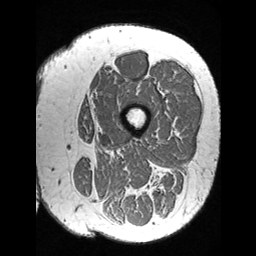

(a) Image

(b) GT

(c) Baseline

(d) Our method

(e) ResU-Net

(f) AttU-Net

(g) MC-Net

(h) Fully U

Table 1 lists the quantitative results (evaluated on the testing data) including state-of-the-art approaches for the following methods: U-Net (Baseline) [5], ResU-Net [7], AttentionU-Net [6, 22], MC-Net [15], a fully supervised U-Net, and our proposed method. Qualitative results are shown in Fig. 3. When only labeled 2D samples were available for training, the proposed method outperformed all the compared methods with an improvement of the and metrics of and when compared to the baseline. Furthermore, our method proposal with a low number of samples gave results comparable to those of a fully supervised U-Net trained with labeled samples.